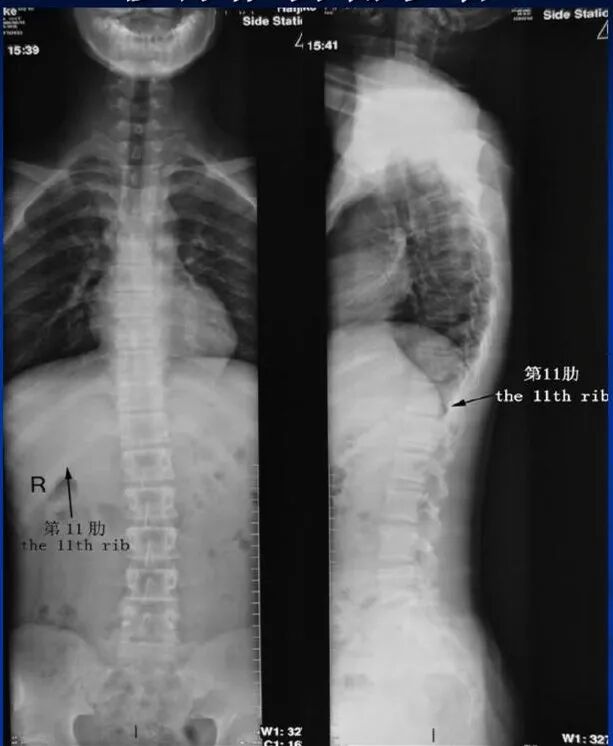

该设备属于多功能X线机,除具有传统数字胃肠机所有功能外,还有DR平板探测器X线摄影所有功能,主要用于消化道气钡双重对比造影、全脊柱拼接摄影、全下肢拼接摄影、ERCP、泌尿系造影、“T”管造影、钡剂灌肠、四肢造影、子宫输卵管造影等各类检查,是检查消化道溃疡、肿瘤、异物等疾病的主要方法之一。

在全脊柱拼接摄影、全下肢拼接摄影方面,亦能弥补其他检查设备的不足。

下图为开展全下肢拼接摄影图像、全脊柱拼接摄影图像

在临床方面,强大的图像处理功能可以完成临床各种造影的需求。